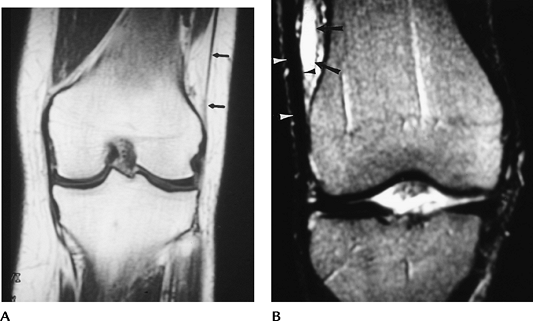

FIGURE 5-78 Iliotibial band syndrome. (A) Normal coronal image of the iliotibial band (arrows). (B) Thickened band (arrowheads) and fluid collection (arrow) on a T2-weighted coronal MR image in a patient with iliotibial band syndrome.